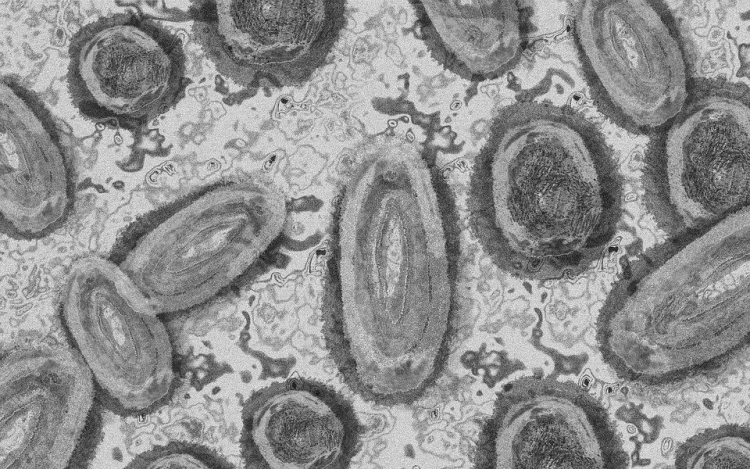

Forrás: mti/illusztráció: pixabay

Egy 3 év alatti gyermek fertőződött meg majomhimlővel Belgiumban

Belgiumban egy 3 év alatti gyermek fertőződött meg majomhimlővel - számolt be róla szerdán a Sudinfo hírportál.

Steven Van Gucht, a belga közegészségügyi intézet (Sciensano) fertőző betegségekkel foglalkozó osztályának vezetője azt nyilatkozta, hogy nagyon kivételes esetről van szó, a gyermeket valószínűleg saját szülei fertőzhették meg. Véleménye szerint nagyon ritka, hogy a fertőzés szülőről gyerekre terjed, de előfordulhat. Mint mondta, a gyermekek tünetei általában enyhék.

"A betegségben szenvedőknek nagyon kell vigyázniuk, hogy ne fertőzzék meg gyermekeiket. Akár egy törölközővel is át lehet adni a fertőzést" - magyarázta Marc Van Ranst virológus professzor a helyi sajtónak. Európában eddig 29 fertőzést igazoltak gyermekeknél.

Belgiumban a járvány kezdete óta 671 majomhimlős esetet regisztráltak a Sciensano kedden közzétett adatai szerint. 360 fertőzöttet Flandriában, 236-ot Brüsszelben és 75-öt Vallóniában jegyeztek fel, szinte minden érintett 16 és 71 év közötti férfi.

Harmincegy ember került eddig kórházba, egyikük sem szorult intenzív ellátásra. Halálos kimenetelű esetekről nem érkezett jelentés. A Sciensano tájékoztatása szerint a Belgiumban jelenleg rendelkezésre álló 3220 adag majomhimlő elleni oltóanyagból 1153 adagot használtak fel.

Stefaan Van der Borght, a járványkockázat-kezelési csoport (RMG) elnöke arra figyelmeztetett, hogy "a vakcina nem csodaszer," oltás után is fennáll a fertőzés veszélye. "Kerülni kell a betegségben szenvedő emberekkel való érintkezést, és korlátozni kell a szexuális kapcsolatot" - mondta.